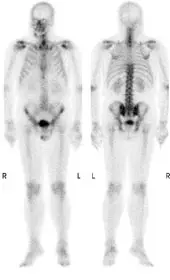

如圖⁹⁹ᵐTc-methylene diphosphonate (⁹⁹ᵐTc-MDP)骨骼造影影像胸椎有一截同位素活性減少,下列何者為最可能的原因?

影像呈現全身骨骼造影(whole-body bone scan)的前位(anterior)與後位(posterior)影像,使用 -MDP 放射性藥物。

影像整體所見:

- 全身骨骼放射性藥物分布整體均勻,可見腎臟(kidneys)及膀胱(bladder)的正常生理性攝取

- 肋骨(ribs)、胸骨(sternum)、脊椎(spine)、骨盆(pelvis)及四肢長骨(long bones)均可辨識

- 題目說明胸椎(thoracic spine)有一截(segment)同位素活性減少的區域,即局段性光子缺乏區(segmental photopenic defect)

局段性胸椎光子缺乏(segmental photopenia)的影像特徵:

- 呈現為脊椎某一段連續節段的攝取明顯低於相鄰椎體

- 邊界通常清晰(sharply demarcated),與放射治療